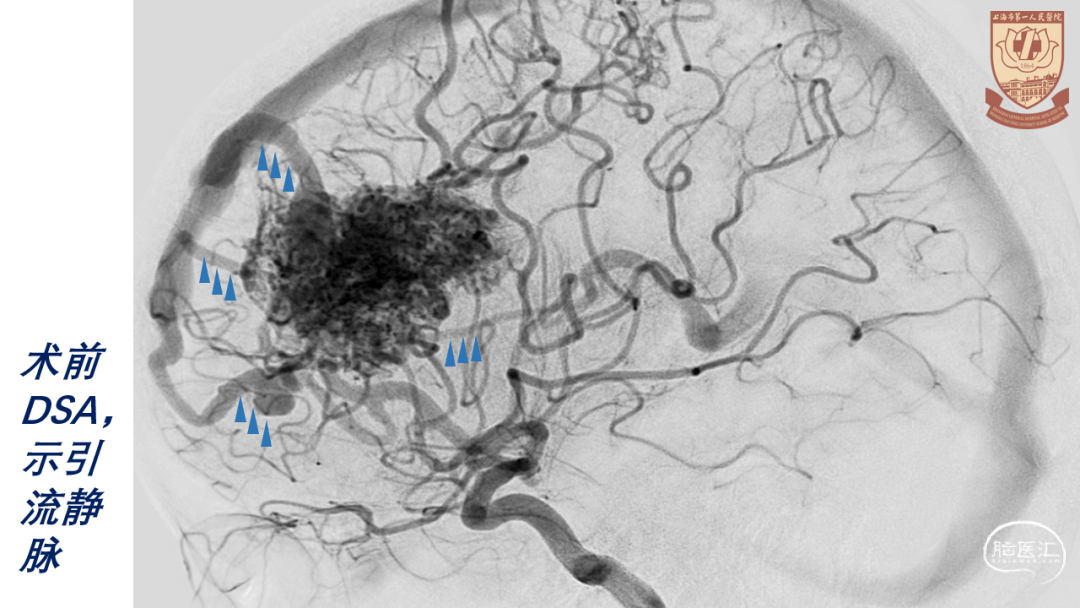

nidus构筑

引流静脉:

内侧面:额内侧静脉(前、中、后)

深部:大脑内静脉-Galen静脉

因A3远段已栓塞,可早期切断纵裂面前、中引流静脉,增加前纵裂显露

术中需识别所有主供血动脉和引流静脉

最后切断主引流静脉